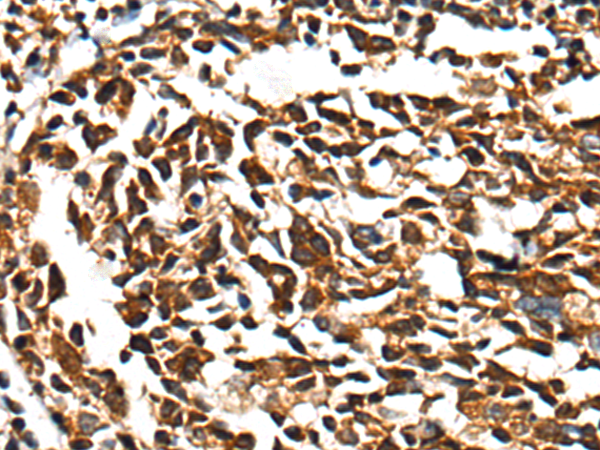

IHC positive control: |

Human lung cancer and human tonsil |